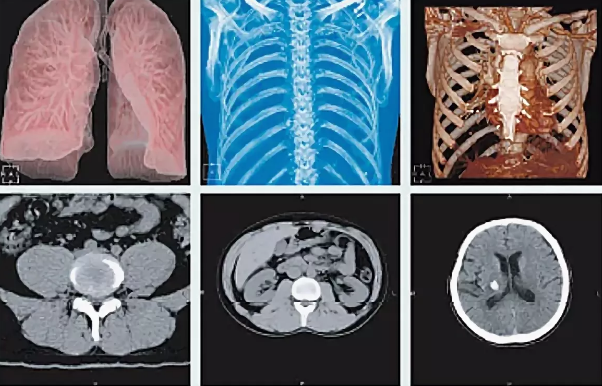

Томограф Philips Ingenuity Elite дает возможность получать высококлассную визуализацию при сниженной лучевой нагрузке в ряде педиатрических исследований, в том числе для диагностики патологии брюшной полости, легких, сосудов и костной системы в ортопедии и травматологии. В числе основных преимуществ аппарата – технология IMR, которая позволяет специалистам получать практически бесшумные изображения с существенно более низкой лучевой нагрузкой и сохранением диагностического качества визуализации. Благодаря улучшенной визуализации мелких деталей технология IMR дает уверенность в правильности полученных показателей. Массив полученных данных обрабатывается на рабочей станции IntelliSpace Portal IX, что обеспечивает высокую продуктивность работы отделения.

Четвертое поколение технологии снижения дозы iDose4 позволяет существенно снизить уровень шума на изображениях и заметно улучшить визуализацию мягких тканей и сосудов при снижении дозы на величину до 80%.Превосходные клинические возможности, ориентация на пациента, высокая рентабельность, а также низкая доза — все это Ingenuity. Никаких компромиссов.

Клинические возможности

- Увеличение пространственного разрешения при том же уровне дозы на величину до 68%

- Снижение лучевой нагрузки на величину до 50 % при увеличении пространственного разрешения на величину до 35%

- Снижение лучевой нагрузки на величину до 80% при том же диагностическом качестве изображений

- Персонализированные инъекции контрастного вещества для поддержания стабильно высокого качества изображений